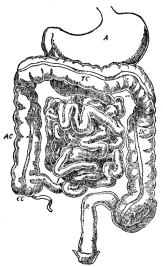

As an introduction to this topic a word may be said about the wide differences of complexity that are found in animals. They range from the simplest imaginable, a single cell with its nucleus and with protoplasm that appears almost uniform throughout, to a highly organized body like that of man, composed of millions of cells of many different kinds. Between these extremes almost every possible form is seen. The one-celled animals themselves show a wide range of complexity, and as soon as animals begin to be formed of numbers of cells grouped together the possibilities of complexity increase in proportion. One important difference between one-celled and many-celled animals needs to be emphasized; that is the matter of size. There are definite limits to the size that a single cell may attain; these limits are just over the boundary of naked eye vision. If animals are to attain larger sizes, they must necessarily be composed of many cells. The life of a single-celled animal presents no special problem, since it has only to take in through its outer layer from the surrounding water the various food materials and the oxygen which its metabolism requires, and to discharge into the same water any chemical products that may result from that same metabolism, and the question of whether it will live or die depends only on whether the water in which it happens to be contains sufficient materials and is otherwise suitable as a place to live. A many-celled animal, whose cells are arranged in not more than two layers, is in practically the same situation, for every cell has a frontage on the water and so can carry on interchanges of material directly; but the moment complexity reaches a stage where any cells are buried beneath other cells some special arrangement must be provided so that the buried cells can obtain the needed substances for their metabolism. The arrangement consists, in general, of furnishing what may be called an internal water frontage for the buried cells. In other words, complex animals have spaces all through their bodies, and these spaces are filled with fluid. There are no living tissues so dense that the cells of which they are composed are completely cut off from contact with body fluid. In thinking of our own bodies we should realize that this same arrangement applies; every one of our millions of living cells has contact with the fluid with which all the spaces of our bodies are filled, and it is from this fluid that the cells obtain the materials for their metabolism, and into this same fluid they discharge whatever substances their metabolism may produce.

The total amount of body fluid is not large, for the spaces among the cells are in most cases extremely tiny; it follows that with all the millions of cells absorbing food materials and oxygen from this fluid and discharging waste materials into it the time will soon come when no more food or oxygen will be left to be absorbed and there will be no more capacity for holding waste substances. If this state of affairs were actually to happen, metabolism would come to an end and death would be the result; evidently there must be some means of keeping the body fluids constantly renewed in respect to the things which the cells need for their metabolism, and constantly drained of the waste substances which the cells pour out. The way in which this renewal is accomplished is simple; part of the body fluid is separated off from the rest in a system of pipes, known to us as the blood vessels, and this part is kept in motion; at intervals along the system are stations at which the moving fluid can exchange substances with the fluid which actually comes in

contact with the cells; thus the stationary fluid can obtain from the moving fluid the materials which the cells, in turn, are constantly withdrawing from it, and can pass on to the moving fluid the products with which the cells are continuously charging it. All that is necessary to complete the successful operation of the system is to have additional stations at which the moving fluid can obtain supplies of food materials and of oxygen, and stations where it can get rid of the wastes which it accumulates from the stationary fluid, and there must be a pump by which the moving fluid is kept in motion. We are familiar with the moving fluid under the name of blood; the system of pipes in which it moves are the blood vessels; the pump which keeps it in motion is the heart; the various supply stations include the digestive organs, the lungs, and the kidneys. In later chapters the operation of all these stations will be described in detail. The present outline has been given to show in a general way how the problem of metabolism is handled in highly organized bodies in which the individual cells have no direct access to food or oxygen supplies.